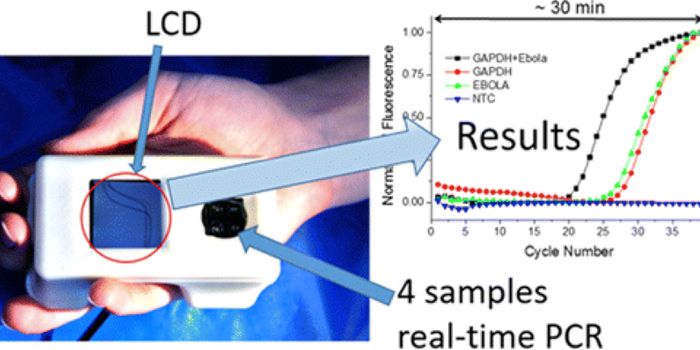

APR 15, 2021Clinical & Molecular DXDuke University scientists have created a highly sensitive Ebola virus portable diagnostic device, 1000 times more sensi ...

APR 29, 2016Clinical & Molecular DXEbola infection and transmission caused a huge international health crisis in 2015 in West Africa, the site of the large ...